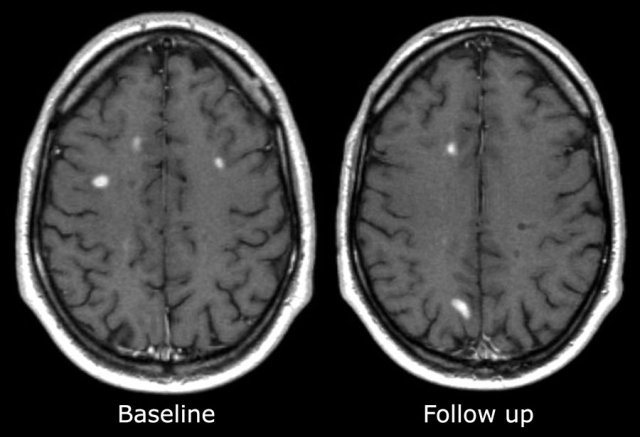

These are images of a patient who was re-examined 3 months after the first clinical attack.

Typical findings for MS as seen in this case are:

- Multiple enhancing lesions

- Many of these lesions 'touch the cortex' and must be located in the U-fibers.

- These enhancing lesions all are new lesions, since Gadolinium enhancement is only visible for about 1 month.

- So this finding is proof of dissemination in time.